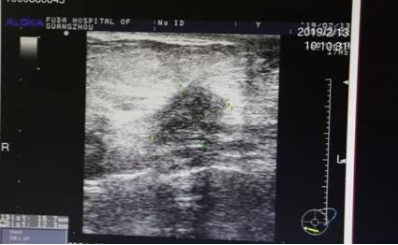

来到复大肿瘤医院,医生们首先为Seekree女士做了检查,确定了她的肿瘤是一点五公分,分界不清,比较明确是乳腺癌了。

主刀医生副院长牛立志教授介绍:“因为这位英国女士的本人只接受冷冻治疗,我们选择在冷冻手术中同时取活检,活检证明她确实是乳腺癌。手术中,我们插了两根针,把她的肿瘤完全覆盖,冰球逐渐扩大让肿瘤完全冻死。术后三天,她就可以出院回家了。”